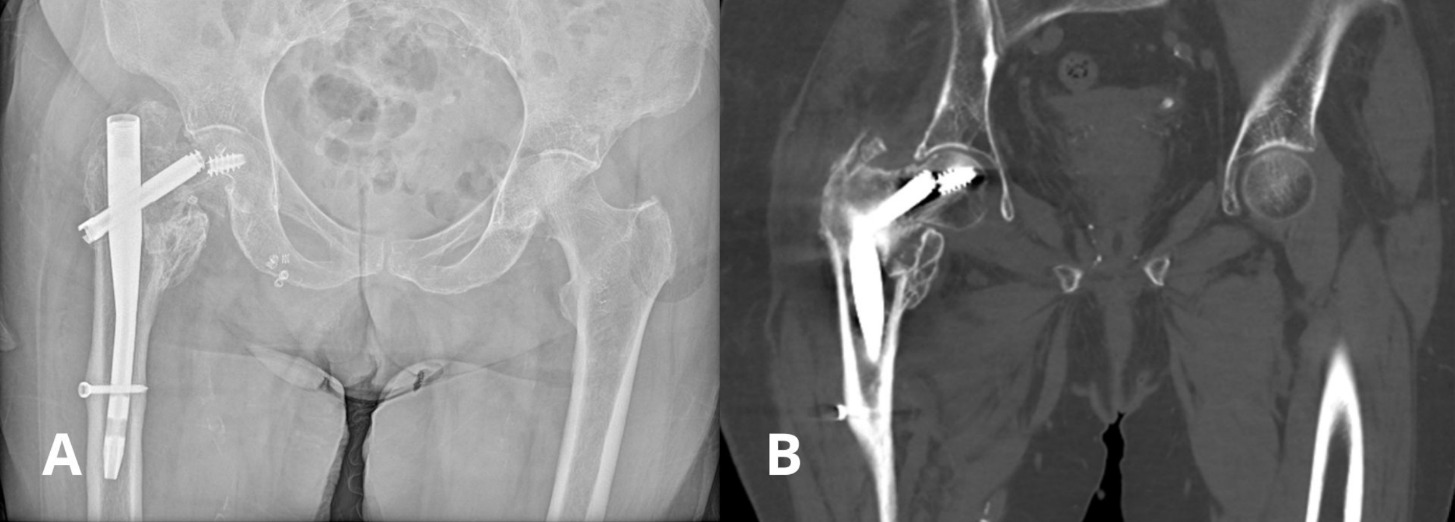

After the diagnosis of the patient’s current injury, she was admitted for revision surgery. Intraoperatively, the previously implanted cephalomedullary nail was extracted, including the fractured cephalic lag screw and femoral head to allow for reconstruction. Given the patients’ advanced age, poor bone quality, and the nature of the injury, the surgical team decided to proceed with a cemented total hip arthroplasty (THA). The choice of THA was made due to re-fixation not being a viable option given the location of the new fracture and her osteoporosis. In addition, a dual mobility implant was chosen to decrease the possibility of postoperative dislocation. Unfortunately, the patient intraoperatively suffered a simple spiral supracondylar femoral fracture while removing the intramedullary nail. The intraoperative fracture was addressed with internal fixation using two interfragmentary lag screws and a long supracondylar locking plate. Next, the acetabular and long femoral component were cemented in place, and after inserting the dual mobility bearing, hip stability was confirmed. Intraoperative fluoroscopy was used to evaluate correct positioning of the implant at the end of the procedure. Figure 3 depicts the retrieved implant and the femoral head, as well as the immediate postoperative radiographic image.